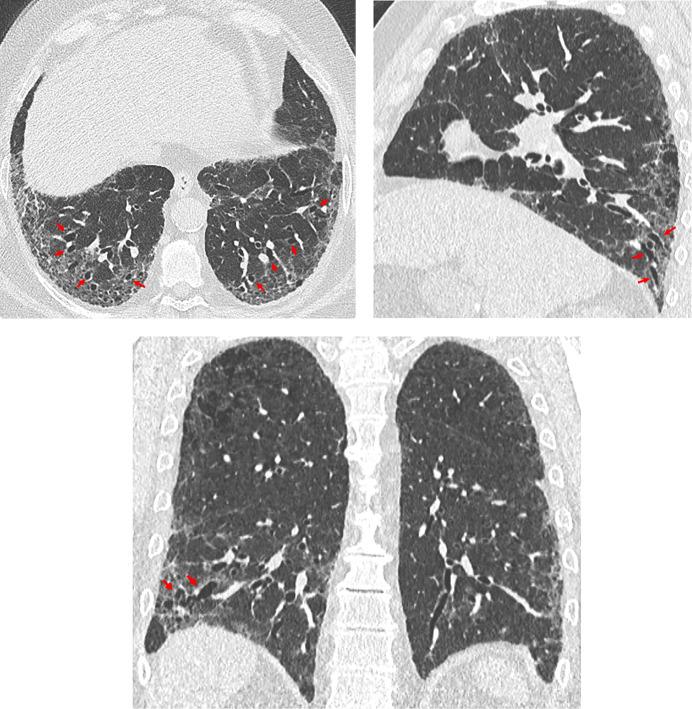

This American Thoracic Society, European Respiratory Society, Japanese Respiratory Society, and Asociación Latinoamericana de Tórax guideline updates prior idiopathic pulmonary fibrosis (IPF) guidelines and addresses the progression of pulmonary fibrosis in patients with interstitial lung diseases (ILDs) other than IPF. A committee was composed of multidisciplinary experts in ILD, methodologists, and patient representatives. ) Update of IPF: Radiological and histopathological criteria for IPF were updated by consensus. Questions about transbronchial lung cryobiopsy, genomic classifier testing, antacid medication, and antireflux surgery were informed by systematic reviews and answered with evidence-based recommendations using the Grading of Recommendations, Assessment, Development and Evaluation (GRADE) approach. ) Progressive pulmonary fibrosis (PPF): PPF was defined, and then radiological and physiological criteria for PPF were determined by consensus. Questions about pirfenidone and nintedanib were informed by systematic reviews and answered with evidence-based recommendations using the GRADE approach. ) Update of IPF: A conditional recommendation was made to regard transbronchial lung cryobiopsy as an acceptable alternative to surgical lung biopsy in centers with appropriate expertise. No recommendation was made for or against genomic classifier testing. Conditional recommendations were made against antacid medication and antireflux surgery for the treatment of IPF. ) PPF: PPF was defined as at least two of three criteria (worsening symptoms, radiological progression, and physiological progression) occurring within the past year with no alternative explanation in a patient with an ILD other than IPF. A conditional recommendation was made for nintedanib, and additional research into pirfenidone was recommended. The conditional recommendations in this guideline are intended to provide the basis for rational, informed decisions by clinicians.

美国胸科学会、欧洲呼吸学会、日本呼吸学会和拉丁美洲胸科学会更新了特发性肺纤维化(IPF)指南,涵盖了除 IPF 以外的间质性肺疾病(ILD)患者肺纤维化的进展。一个委员会由ILD 的多学科专家、方法学家和患者代表组成。

• 更新 IPF:通过共识更新了 IPF 的放射学和组织病理学标准。关于经支气管肺冷冻活检、基因组分类器检测、抗酸药物和抗反流手术的问题,通过系统评价提供信息,并使用基于证据的推荐和 Grading of Recommendations, Assessment, Development and Evaluation (GRADE) 方法回答。

• 进行性肺纤维化(PPF):定义了 PPF,然后通过共识确定了 PPF 的放射学和生理学标准。关于吡非尼酮和尼达尼布的问题,通过系统评价提供信息,并使用基于证据的推荐和 GRADE 方法回答。

• 更新 IPF:有条件建议将经支气管肺冷冻活检视为具有适当专业知识的中心替代外科肺活检的可接受方法。未对基因组分类器检测提出建议或反对。有条件反对使用抗酸药物和抗反流手术治疗 IPF。

• PPF:PPF 定义为在过去一年中,在非 IPF 的ILD 患者中,出现至少三个标准中的两个(症状恶化、放射学进展和生理学进展),且无其他解释。建议使用尼达尼布,并建议对吡非尼酮进行进一步研究。